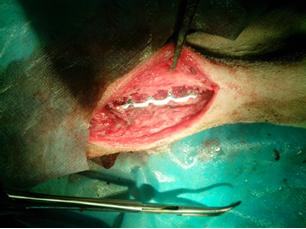

术后叮嘱宠物的主人因为狗的年龄很小,而且阿拉斯加犬又属于大型犬,骨折的内固定会限制以后的生长所以必须及时拆除,但是宠物的主人还是因为工作的原因遗忘了这件事,再把狗带来已经是一个半月以后了,所以对于钢板的拆除很不理想,骨痂已经把骨板包被了,下图为接骨板的拆除过程。那么到底什么时间拆除骨板才是最合适的呢,下面是国外的兽医专家根据经验和实验得出的结论。

手术图

正在进行骨板的拆除,螺钉已被取出